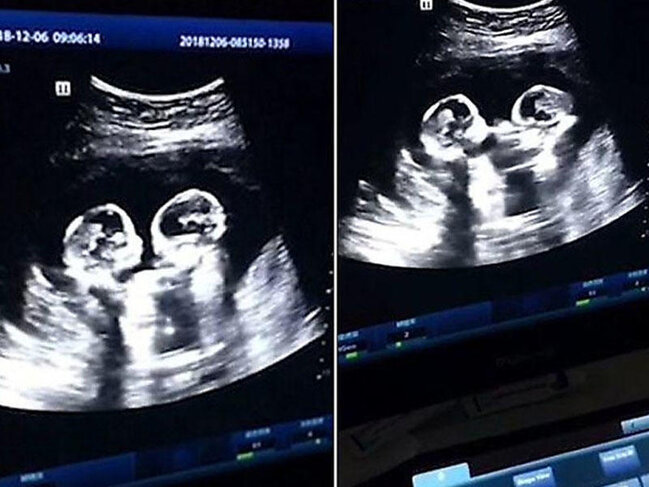

28-yaşlı Tao adlı çinli internetə həyat yoldaşının hamiləlik zamanı USM-nin videosunu yerləşdirib.

Videoda görünür ki, ana bətnində olan əkizlər biri-birini itələyir və vurur.

7News.Az saglamolun.az-a istinadən bildirir ki, uşaqların özünü belə "aqressiv" aparmağının səbəbi onların eyni amniotik kisədə yerləşməsi idir. Əksər hallarda əkizlər ananın bətnində ayrı amniotik kisələrdə yerləşir.

Eyni kisədə yerləşməsi müəyyən təhlükə yaradırdı və bu səbəbdən həkimlər ananın və körpələrin vəziyyətinə daim nəzarət edirdilər.

Uşaqlar keysəriyyə kəsiyi əməliyyatının köməyi ilə dünyaya gəliblər. Hər iki qız sağlam doğulub.